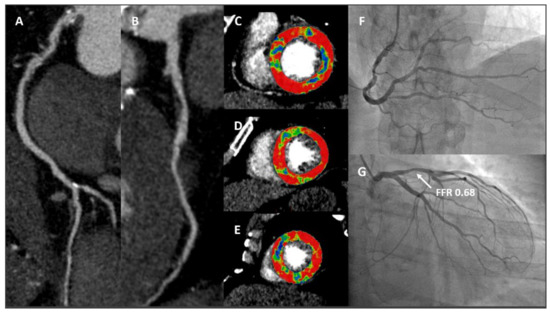

- Pontone, G.; Muscogiuri, G.; Andreini, D.; Guaricci, A.I.; Guglielmo, M.; Mushtaq, S.; Baggiano, A.; Conte, E.; Beltrama, V.; Annoni, A.; et al. The New Frontier of Cardiac Computed Tomography Angiography: Fractional Flow Reserve and Stress Myocardial Perfusion. Curr. Treat. Options Cardiovasc. Med. 2016, 18, 74. [Google Scholar] [CrossRef] [PubMed]

- Pontone, G.; Baggiano, A.; Andreini, D.; Guaricci, A.I.; Guglielmo, M.; Muscogiuri, G.; Fusini, L.; Soldi, M.; Del Torto, A.; Mushtaq, S.; et al. Diagnostic accuracy of simultaneous evaluation of coronary arteries and myocardial perfusion with single stress cardiac computed tomography acquisition compared to invasive coronary angiography plus invasive fractional flow reserve. Int. J. Cardiol. 2018, 273, 263–268. [Google Scholar] [CrossRef]

- Pontone, G.; Baggiano, A.; Andreini, D.; Guaricci, A.I.; Guglielmo, M.; Muscogiuri, G.; Fusini, L.; Soldi, M.; Del Torto, A.; Mushtaq, S.; et al. Dynamic Stress Computed Tomography Perfusion With a Whole-Heart Coverage Scanner in Addition to Coronary Computed Tomography Angiography and Fractional Flow Reserve Computed Tomography Derived. JACC Cardiovasc. Imaging 2019, 12, 2460–2471. [Google Scholar] [CrossRef]